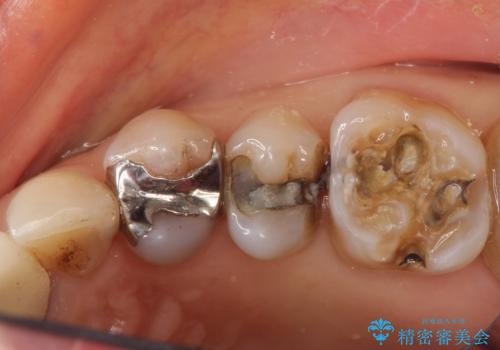

- 定期健診にて虫歯が見つかった患者さんです。県外からお越しいただいている事もあり、かなりお久しぶりの来院でした。歯と歯の間のところと銀歯の下が虫歯になっていました。被せ物はオールセラミッククラウンで治療しました。

銀歯を外すとかなり大きな虫歯になっていました。幸いぎりぎりのところで神経まで虫歯は広がっていなかったため、症状が出ない事を確認した後、オールセラミッククラウンで治療しました。虫歯除去後、残っている歯質が少なかったため、破折抵抗を考慮し部分的な被せ物ではなくクラウンを選択しました。